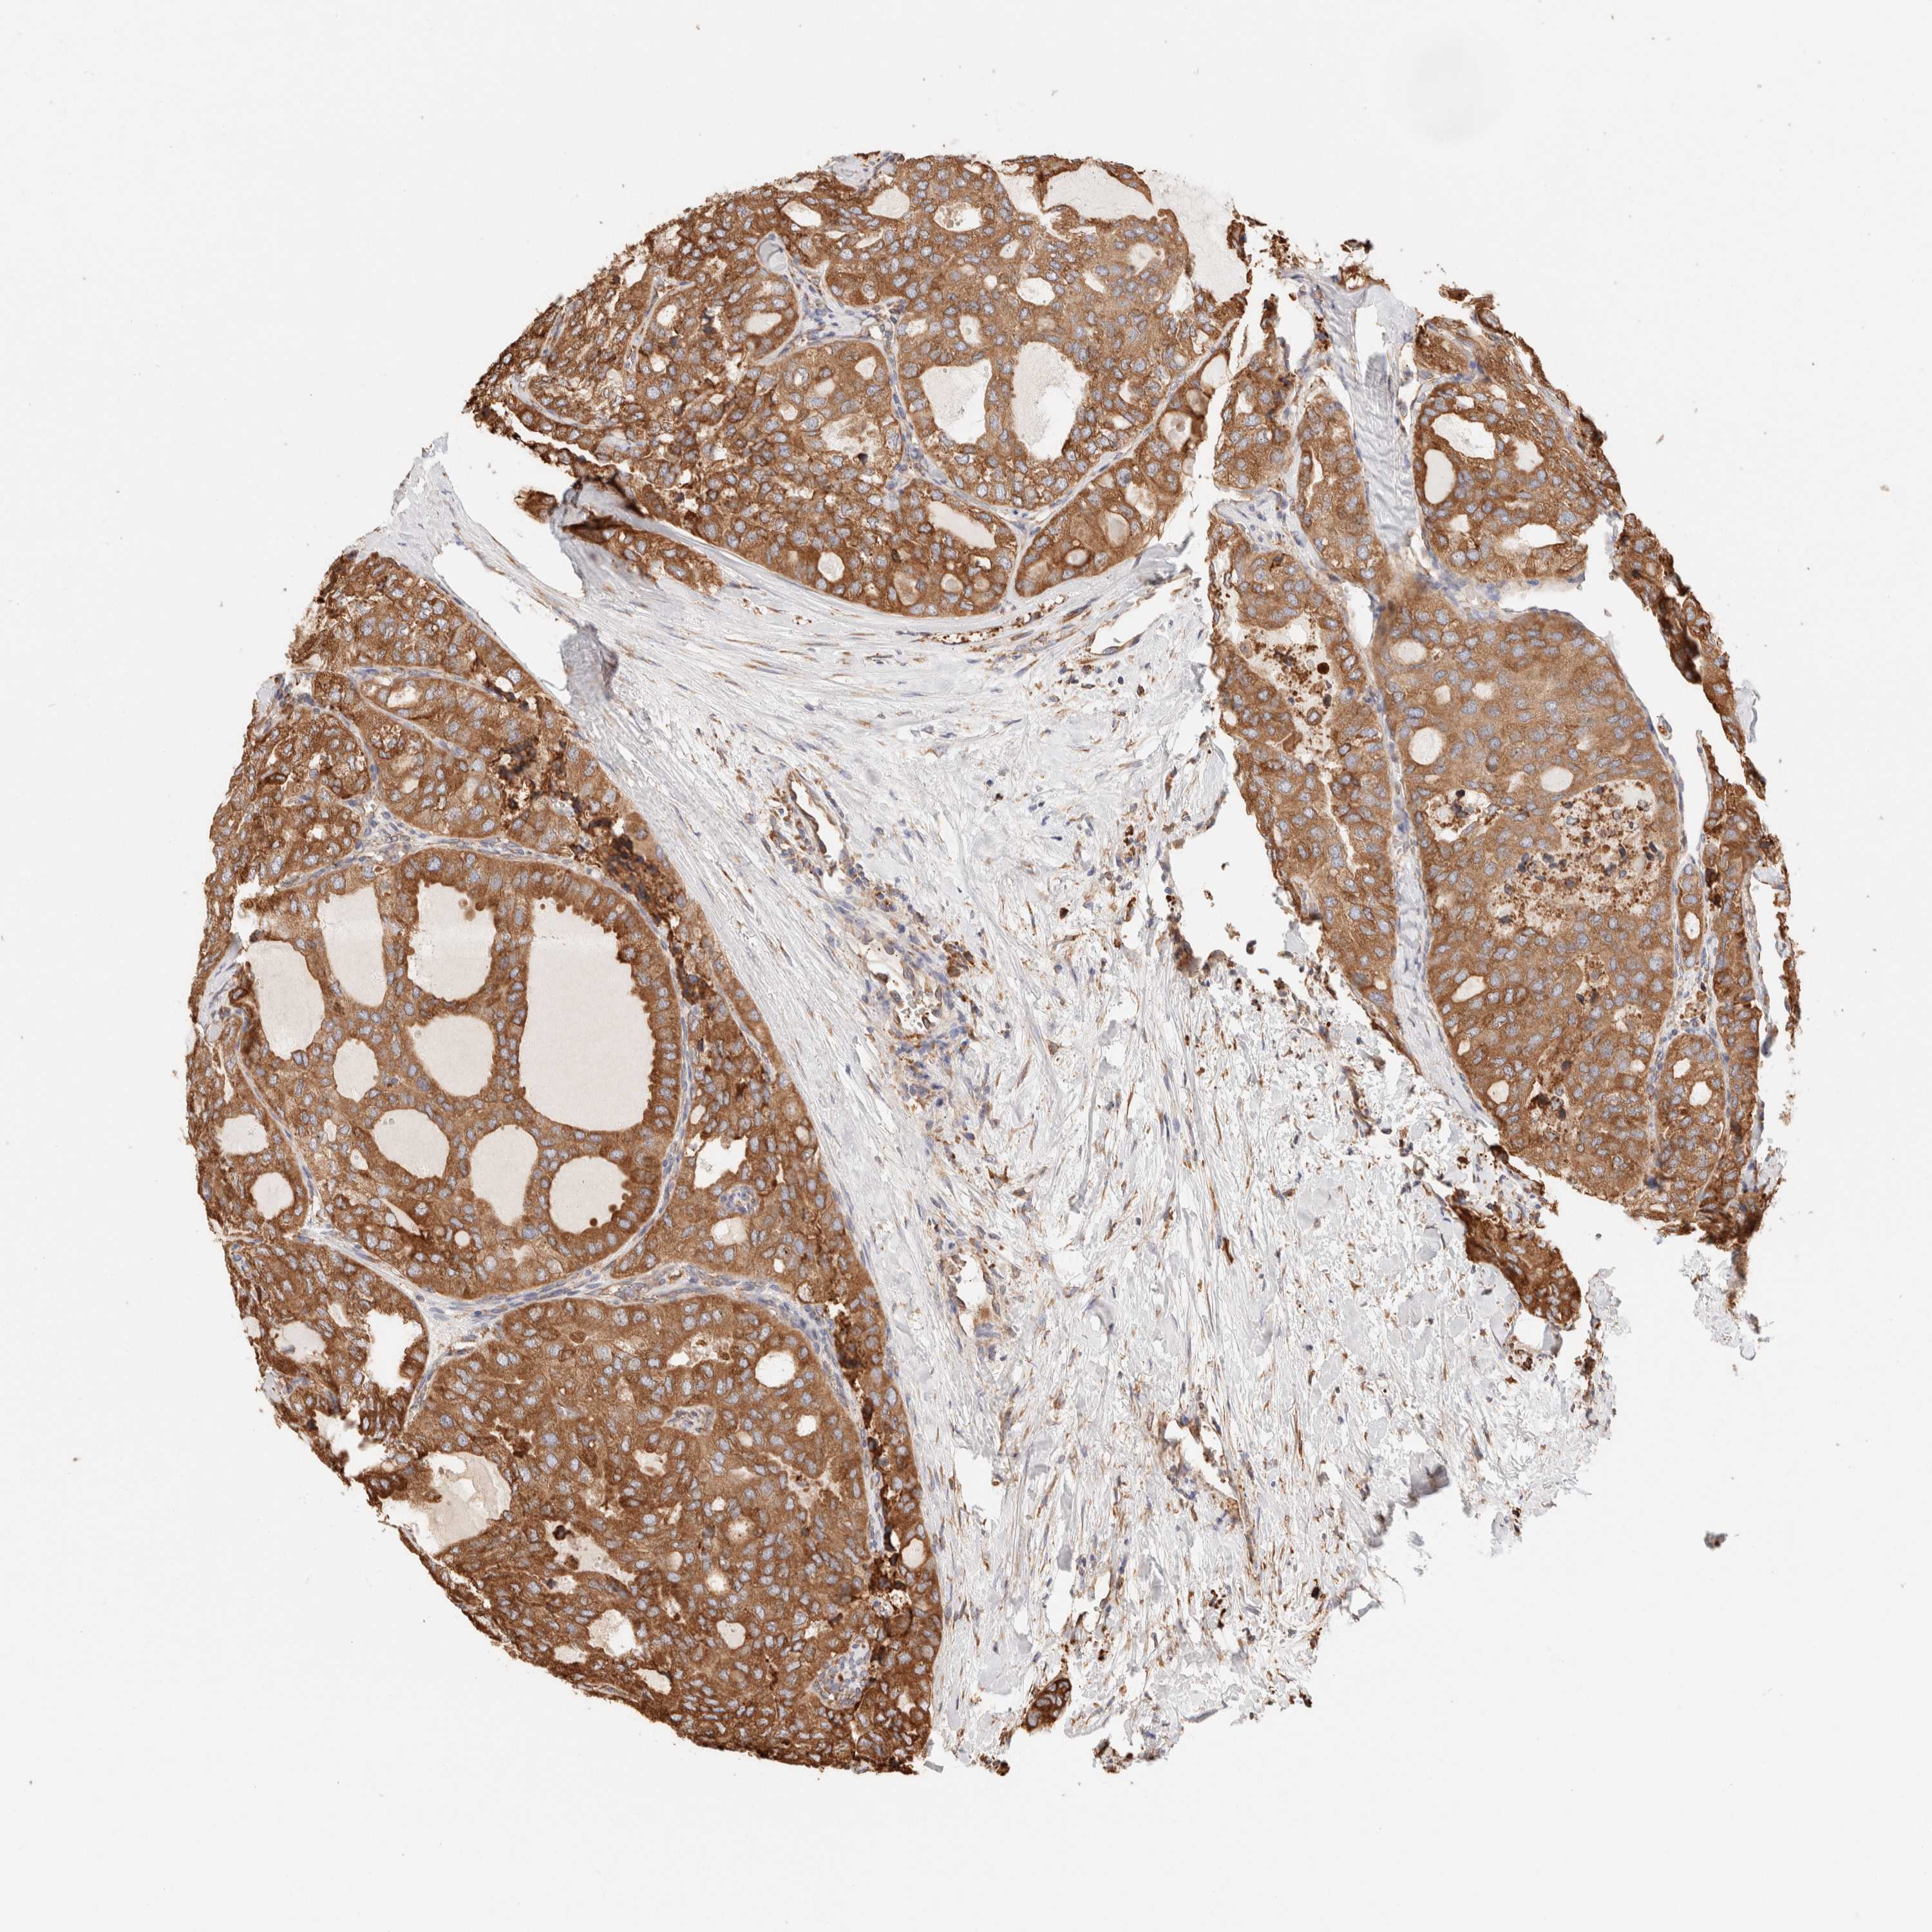

THYROID CANCER - Protein expressioni

A mouse-over function shows sample information and annotation data. Click on an image to view it in a full screen mode. Samples can be filtered based on level of antibody staining by selecting one or several of the following categories: high, medium, low and not detected. The assay and annotation is described here.

Note that samples used for immunohistochemistry by the Human Protein Atlas do not correspond to samples in the TCGA dataset.

Antibody stainingi

Antibody staining in the annotated cell types in the current human tissue is reported as not detected, low, medium, or high, based on conventional immunohistochemistry profiling in selected tissues. This score is based on the combination of the staining intensity and fraction of stained cells.

Each image is clickable and will lead to virtual microscopy that enables deeper exploration of all samples and also displays staining intensity scores, fraction scores and subcellular localization as well as patient and tissue information for each sample.

Antibody HPA007641

Antibody CAB022464

Staining

High

Medium

Low

Not detected

Intensity

Strong

Moderate

Weak

Negative

Quantity

>75%

75%-25%

<25%

None

Location

Nuclear

Cytoplasmic/membranous

Cytoplasmic/membranous,nuclear

Papillary adenocarcinoma, NOS

Follicular adenoma carcinoma, NOS